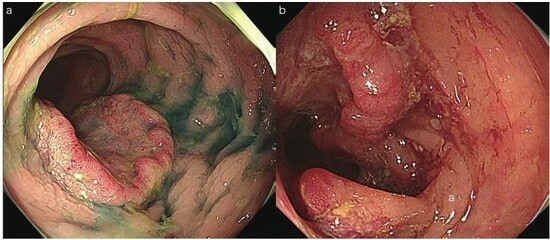

実は、進行大腸がんの人は便潜血検査を2日法で受けても2回とも陰性(正常)の人が1割もいます。早期大腸がんにいたっては、便潜血検査が2回とも陰性の人が4割に上ります。便潜血検査は大腸内視鏡に比べると簡単に受けられる検査ですが、その分どうしても大腸がんの見逃しが多い検査です。残念ながら、毎年便潜血検査が正常で、はじめて便潜血検査が異常となった時に大腸内視鏡を受けたら、進行がんが発見されるということは珍しくありません(図1)。

b) 60歳代男性.便潜血検査は毎年陰性であった.はじめて陽性になった際にはじめて大腸内視鏡を受け、横行結腸に進行した大腸がんが発見された.